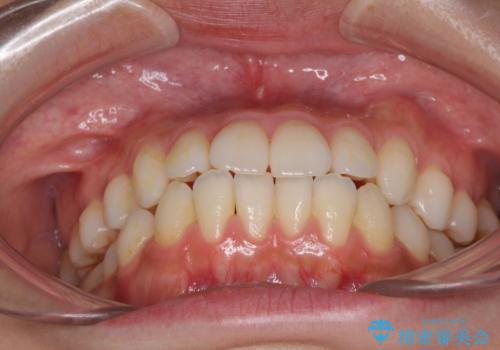

インビザラインで口を閉じやすく

- 下唇に上の前歯が当たることを気にして来院された患者様です。

上顎の親知らずを抜去し、歯列全体を後方に移動させるとともに、IPR(歯と歯の間を削る)を行うことで口元の閉じにくさを改善していくこととしました。

咬合力が強く、マウスピースを介した咬み込みが顕著であったため、奥歯の咬みにくさやIPRのスペースが改善しにくく、治療期間が思った以上にかかってしまいました。